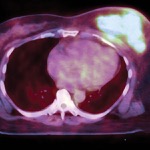

Reexcision Lumpectomies May Not Be Needed for Specific DCIS Cohort

There appears to be minimal difference in 10-year ipsilateral breast tumor recurrence in a specific cohort of ...